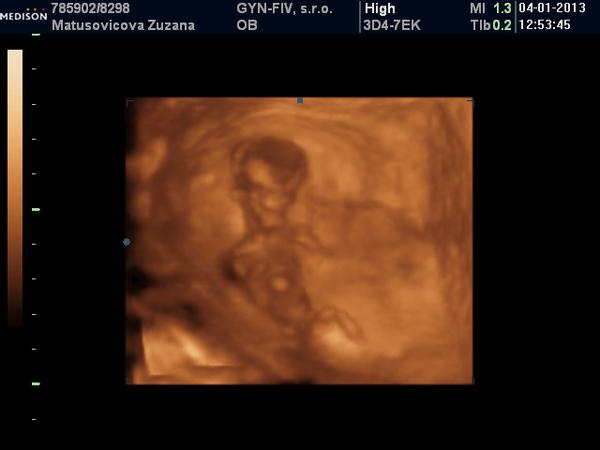

A na gynekológii všetko v poriadku. Bábo má 6,2cm. Som presne 13+0tt. NT nameral 2,2 /na 3D v piatok to bolo 1,5/. Vraj to vyzerá na chlapca, ale to mi napísal s otáznikom. Bol so mnou aj manžel aj Viki a keď vošli dnu, bábo akurát zakývalo, tak sme sa vytešovali 😉. Ale mala som vyšší tlak-140/95. Mám si dávať Magnézium ráno a večer, 3x za deň merať tlak a v piatok tam mám zavolať, že čo a ako. Ak nič, tak v pohode a ak bude vyšší, budeme to potom riešiť.